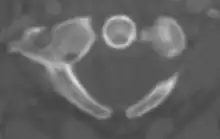

Posterior arch defect on axial CT

Foramen arcuale or a bony bridge above the vertebral artery on the posterior arch of the atlas may be present. This foramen has an overall prevalence of 9.1%.[8] Arch defects refer to the condition where a gap or cleft exists at the anterior arch or posterior arch of the atlas. The prevalence of the posterior arch defect and anterior arch defect was 0.95% and 0.087%, respectively.[9] The anterior arch defect may be presented along with posterior arch defect, a condition known as combined arch defect or bipartite atlas.[10]